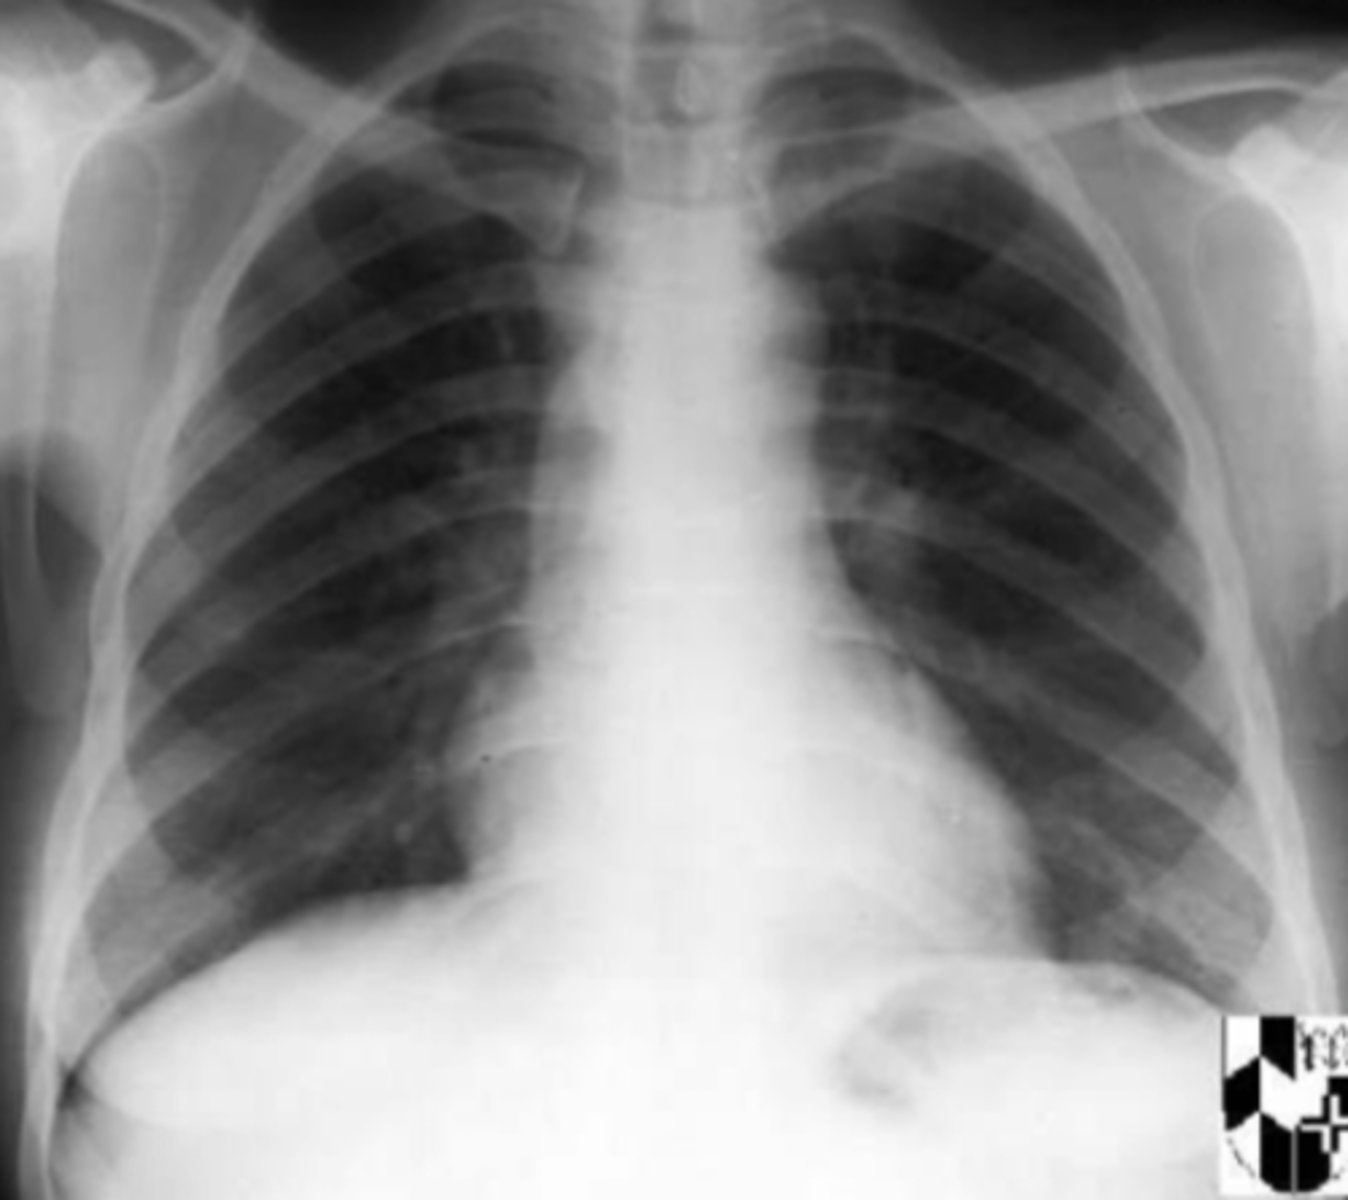

PA of lungs

What view does this show?

AP of lungs